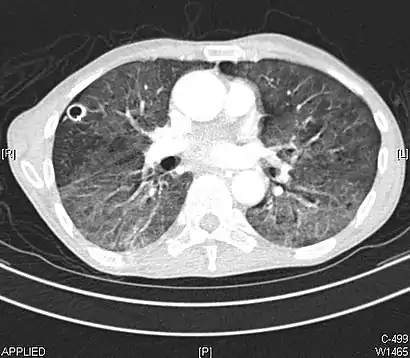

CT image showing ground-glass nodule (circled).

Nodular

There are numerous potential causes of nodular GGOs which can be broadly separated into benign and malignant conditions. Benign conditions potentially leading to the formation of nodular GGOs include aspergillosis, acute eosinophilic pneumonia, focal interstitial fibrosis, granulomatosis with polyangiitis, IgA vasculitis, organizing pneumonia, pulmonary contusion, pulmonary cryptococcus, and thoracic endometriosis. Focal interstitial fibrosis presents a unique challenge when differentiating from malignant nodular GGOs on CT imaging. It is typically persistent over long-term imaging follow-up and shares a similar appearance to malignant nodular GGOs.[9]

Pre-malignant or malignant causes of nodular GGOs include adenocarcinoma, adenocarcinoma in situ, and atypical adenomatous hyperplasia (AAH). One large review study found that 80% of nodular GGOs which were present on repeated CT imaging represented either pre-malignant or malignant growths. Differentiating between pre-malignancy and malignancy on the basis of CT alone can pose a challenge to radiologists; however, there are several features that are indicative of pre-malignant nodules. AAH is a pre-malignant cause of nodular GGO and is more commonly associated with lower attenuation on CT and smaller nodule size (<10 mm) compared to adenocarcinoma.[10] In addition, AAH often lacks the solid features and spiculated appearance that are often associated with malignant growths.[9] In contrast, as adenocarcinoma becomes invasive it will more often cause retraction of adjacent pleura and may show an increase in vascular markings. Nodules >15 mm almost always represent an invasive adenocarcinoma.[9][10]